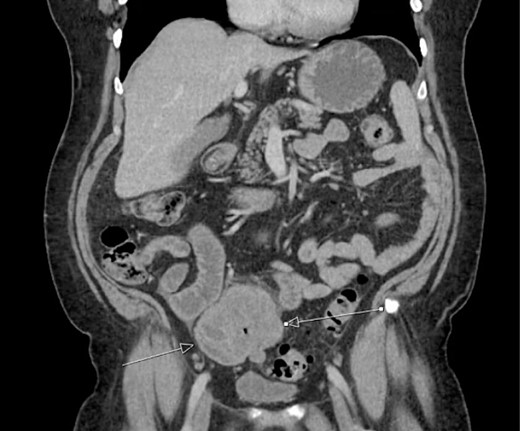

The patient was initially managed nonoperatively with conservative measures including nasogastric (NG) tube decompression, pain control, and serial abdominal exams. Surgery was consulted once CT imaging was obtained (Figs 1–3) and recommended that the patient undergo surgery to resect the identified mass and relieve the obstruction. During the surgical exploration, a mass originating from the terminal ilium was identified that was densely adhered to the peritoneum, bladder, and sigmoid colon, requiring careful dissection. The mass, three lymph nodes, and 29 cm of associated small bowel segment was resected with grossly negative margins, with the mass measuring 7 cm × 8 cm × 9.5 cm. A side-to-side anastomosis was created and the specimens were sent to pathology for further investigation. Postoperatively the patient was hospitalized for 7 days for pain control and monitoring. On postoperative day eight he was discharged with follow up appointments with oncology, general surgery, and a referral to an academic cancer center.

Initial CT imaging, coronal cut, showing necrotic mass causing small bowel obstruction.